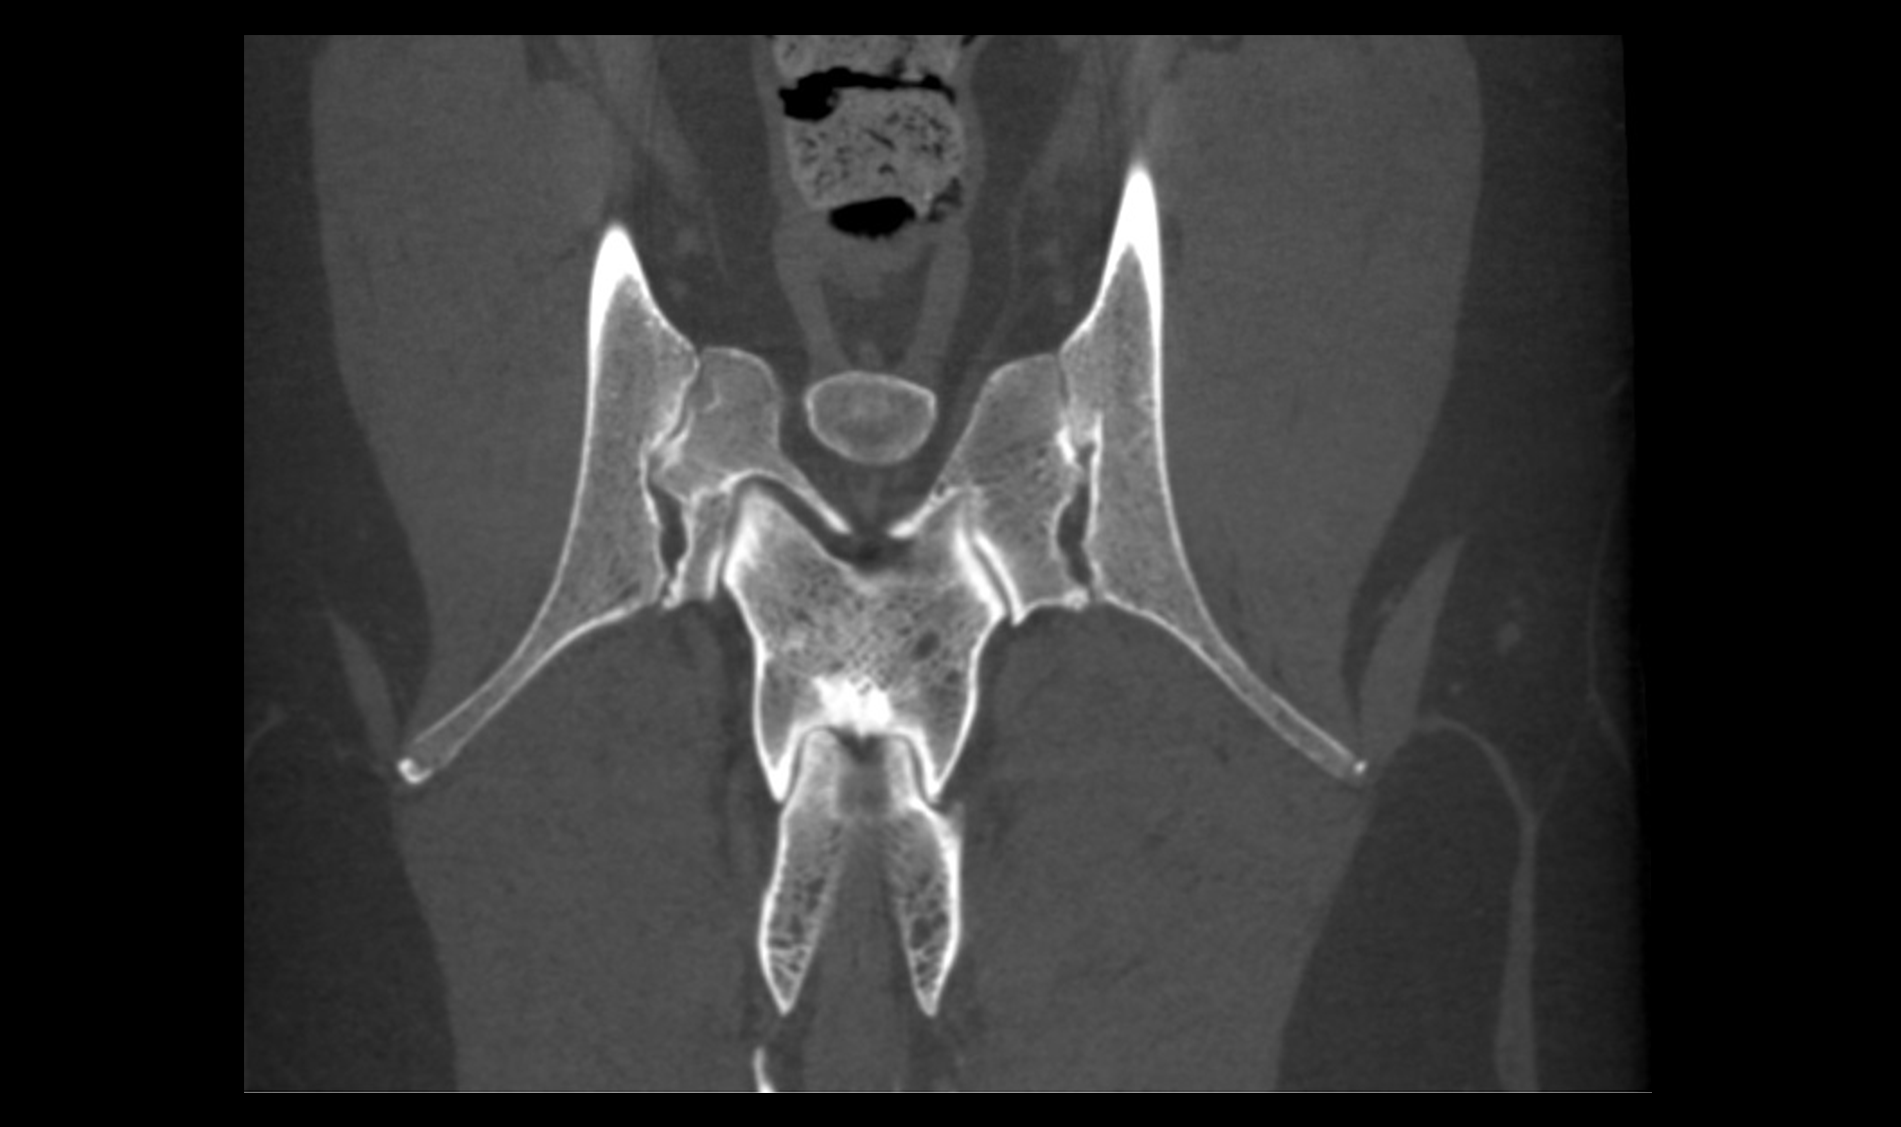

MOBILE IMAGING

Easily move our technology from the diagnostic space to the surgery room.

FULL INTEGRATION WITH DELPHI NAVIGATION SYSTEM

Our devices + Delphi navigation system are the ultimate expression of the intraoperative experience

Diagnosis

Accurately diagnose medical conditions in-house, thereby helping treatment, increasing the number of surgeries and improving patient care.

Surgeries

Our devices can follow the patient through the pre-operative, intra-operative and post-operative phases. Our technology will guide you every step of the way.